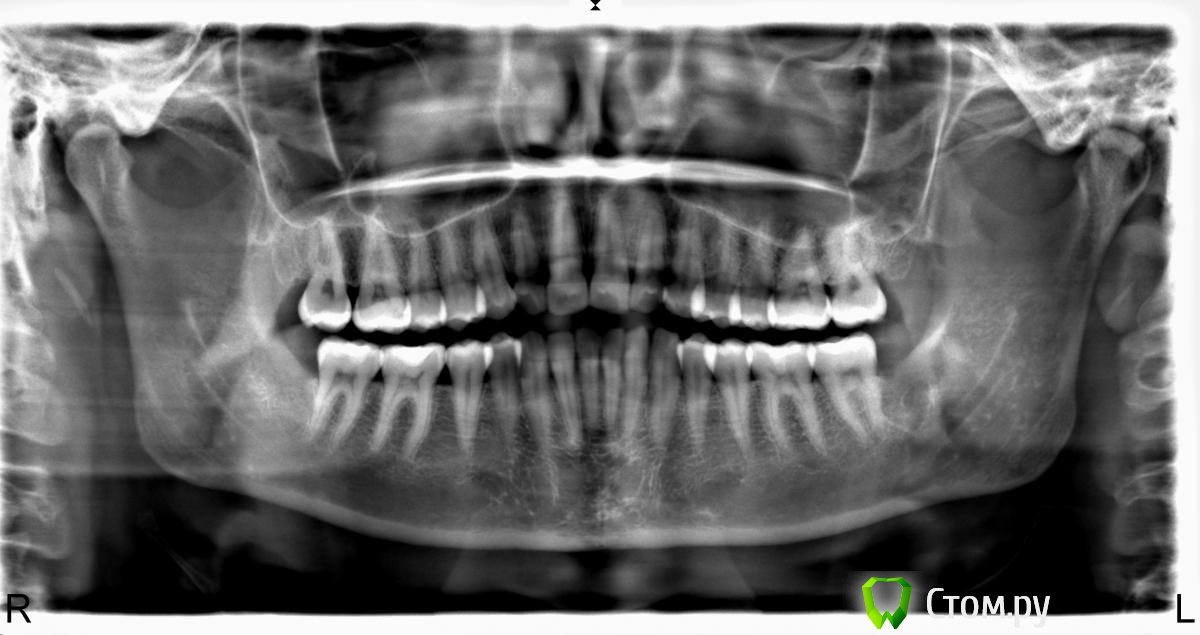

Алина-малина Опубликовано 29 января, 2014 Автор Поделиться Опубликовано 29 января, 2014 И еще вот на всякий случай Ссылка на комментарий